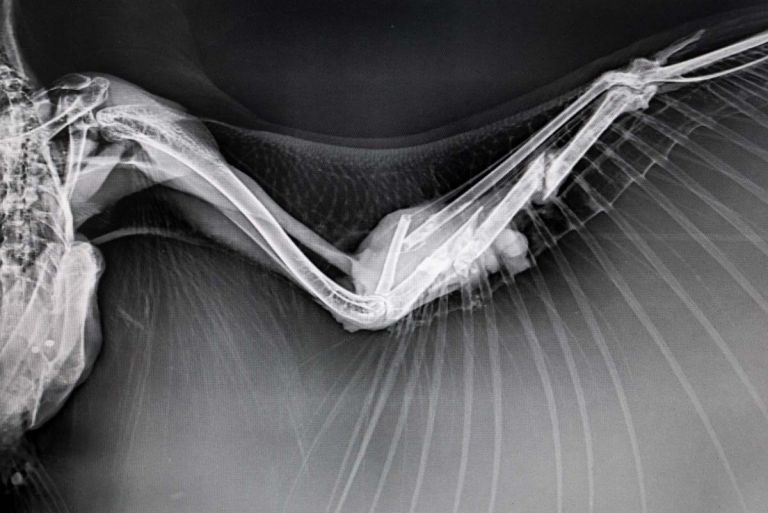

This is a story about transformation—not just of the owls, but of the women themselves. Across cultures, owls have long been associated with mystery, death, and darkness. Yet through this project, I seek to capture the tension between these enduring myths and the quiet, determined joy of grassroots conservation. Happiness, in this context, is not loud or performative; it is the warmth of a healed wing, the first flight of a recovered bird, the defiance of fear through knowledge and care.